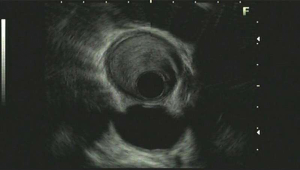

Upper gastrointestinal tract endoscopy disclosed a giant submucosal mass with a smooth surface that was located 18 to 40 cm from the incisors. Multiple biopsy specimens revealed inflamed mucosa with hyperaemia. There was no evidence of malignancy. Ultrasonic gastroscopy disclosed a giant protrusion of the esophagus located 18 cm from the incisors that originated from the submucous and was suspected to be a neurofibroma because of its homogeneous and hypoechoic lesion with clear margins. Distal esophagus and gastroesophageal junction was normal (Figures 1,2). A barium swallow showed a large intraluminal mass of the upper esophagus and compensatory dilatation of the proximal esophagus. A slightly irregular mucosal surface indicated a probable benign esophageal tumor (Figure 3). The patient underwent cervical, cardiac and abdominal ultrasound, which were unremarkable. Blood counts, biochemistry values and tumor markers levels were all found to be within normal limits.